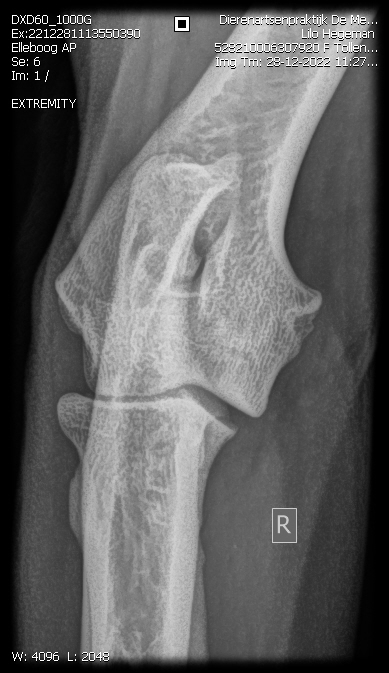

Eerste Gezondheidsresltaten Tollentler

Lilo onze eerstgeborene Tollentler in de kleur Tan is inmiddels volledig getest.

Zo ook het overige. Zie onderstaand.